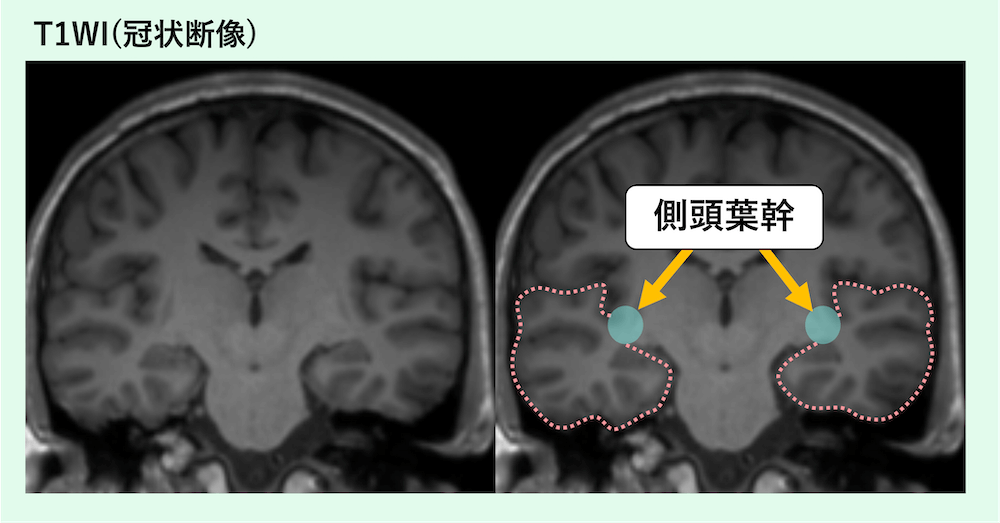

側頭葉幹の正常解剖

- 冠状断像が正常解剖の把握に特に重要。

側頭葉の根や茎のように見える白質部分が側頭葉幹です。